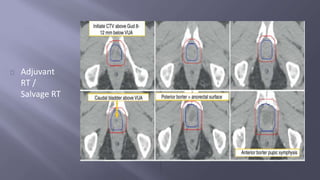

Adjuvant

RT /

Salvage RT

Indicated in adverse path features ; detectable PSA with no evidence of

disseminated disease

Usually given within 1 year after RP and once operative side effects are

minimized

Salvage therapy is indicated in detectable PSA that increases on 2 subsequent

occasions . Most effective if pre treatment PSA is < 1 ng /ml

Recommended dosage : 64 to 68 Gy in std fractionation

Defined target volume is the prostate bed

Inclusion of pelvic nodes can be considered but not necessary.